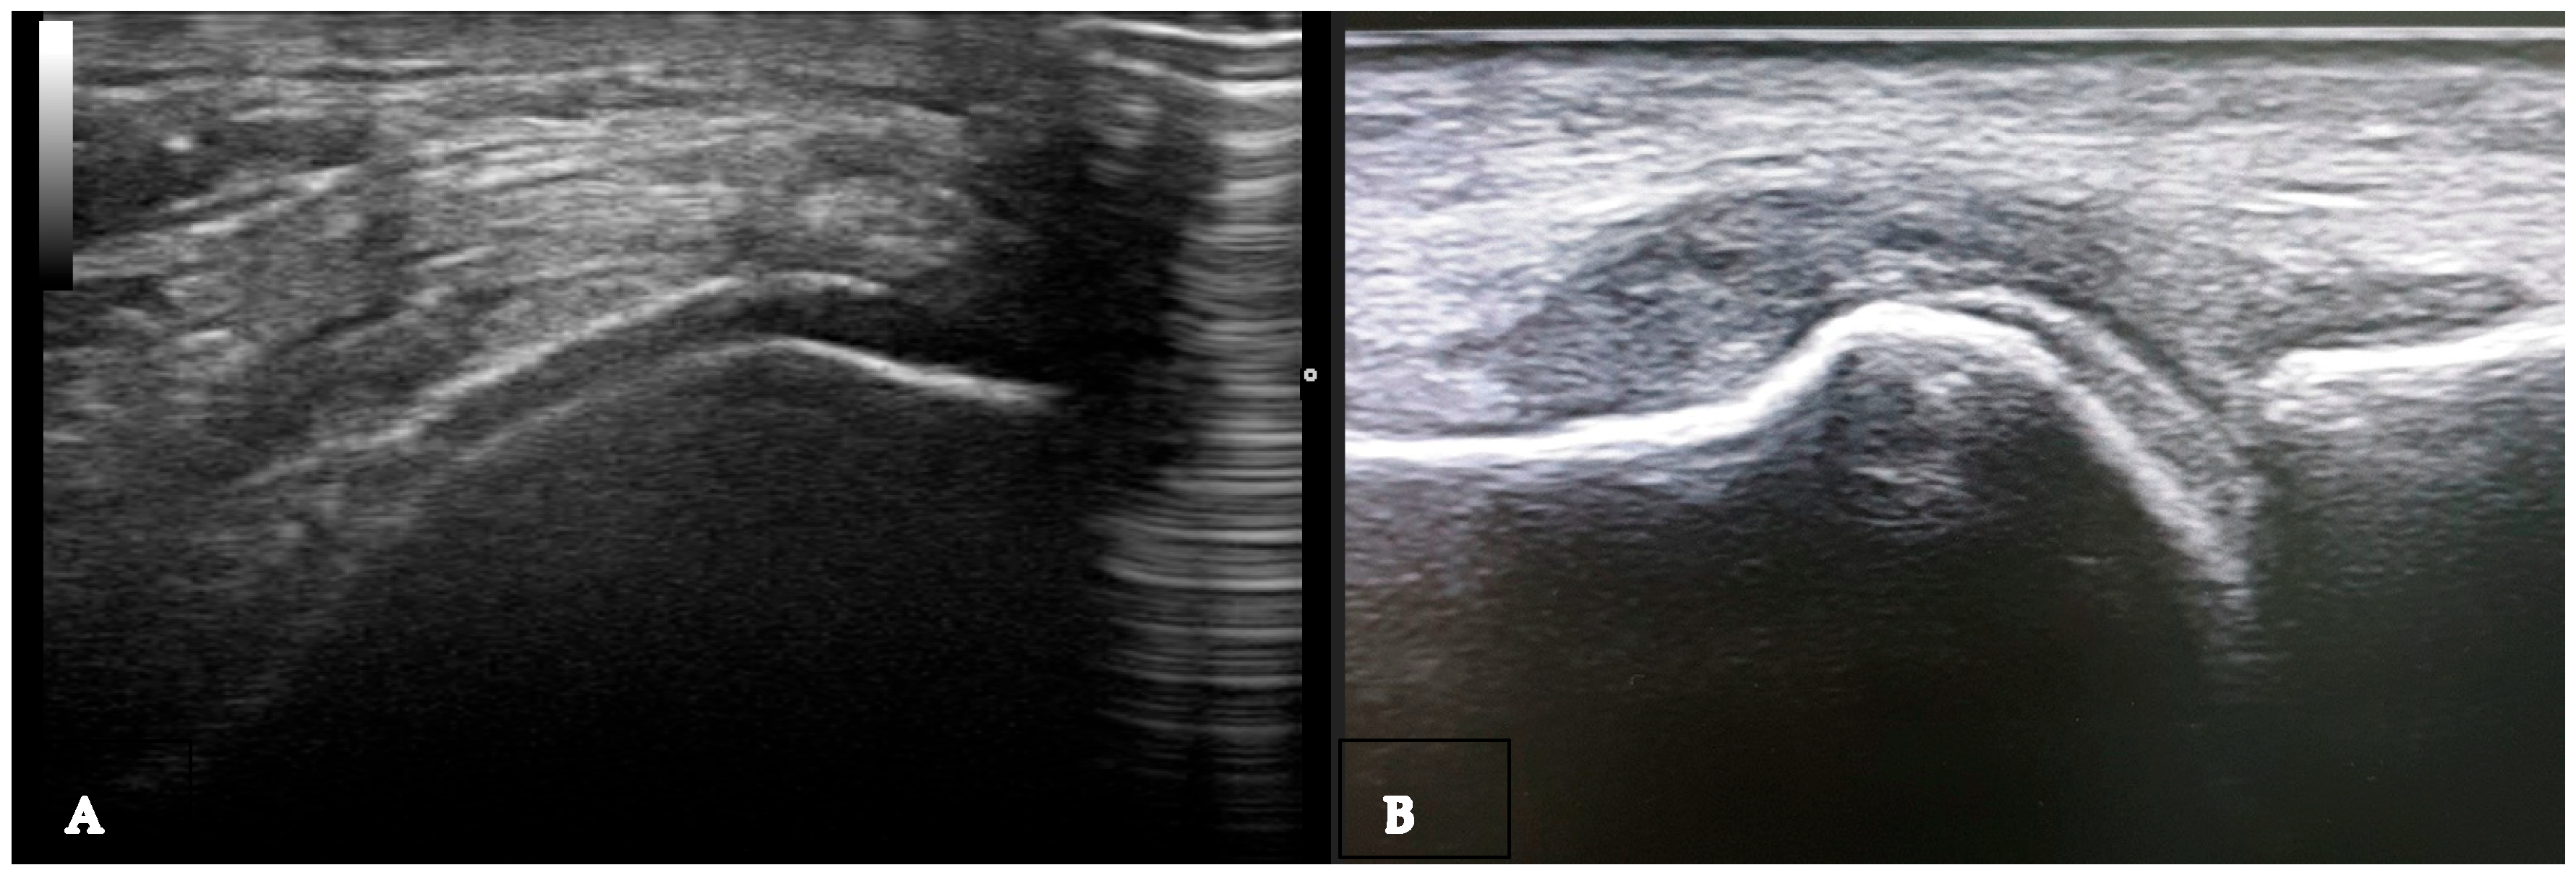

Figure 6.

Ultrasound features of “double contour sign” visible on the cartilage surface of the femur (A) and first metatarsal bone (B).

The double contour sign (DCS) indicates deposits of MSU crystals on cartilage surfaces, distinguishable from calcium pyrophosphate crystal deposits typically found within cartilage, highly specific for gout (Figure 2B and Figure 6A,B). Due to MSU crystal deposition, the reflectivity of the chondrosynovial interface is no longer angle-dependent, allowing for easy panoramic visualization of the entire chondrosynovial interface [18,19]. Like the tophus, the DCS should be sought in symptomatic joints, including the first metatarsophalangeal joints (dorsal and palmar planes) and the trochlear cartilage of the knees (suprapatellar plane in maximum flexion). The DCS may be less visible in thin cartilage (tarsal joints) or damaged cartilage, such as in osteoarthritis. Additionally, certain ultrasound features can be mistaken for a DCS, leading to false positives due to several factors: first, the normal hyperechoic appearance of the synovium, where the hyperechoic band appears regular, like a line drawn with a pen. A “true” DCS adheres to the cartilage during dynamic movements. Second, the presence of joint effusion enhances the echo of the posterior wall (increased ultrasound propagation) and may accentuate the normal hyperechoic appearance of the synovium. Finally, thin cartilage (small joints and/or associated osteoarthritis) with chondrocalcinosis and calcium deposits often localized in the intermediate layer of the cartilage [14,16]. Regarding the diagnostic performance of the DCS sign, a recent study by Cipolletta et al. emphasized that dynamic examination significantly improves the effectiveness of US in differentiating between gout and calcium pyrophosphate dihydrate CPPD crystal arthritis. Their results indicated that, with dynamic examination, the DCS sign moved with the cartilage in all cases of gout, whereas it moved in the opposite direction in CPPD patients. [20]. In 2022, Filippou et al. conducted an anatomical cadaver study to compare US DCS findings with pathological features, aiming to evaluate how crystal location affects ultrasound characteristics. The study was performed on upper limb joints until calcium pyrophosphate (CCP) deposits were detected according to OMERACT criteria. The affected joints were then examined pathologically, with crystal deposition described. The findings concluded that monosodium urate (MSU) crystals in gout are located directly on the chondral surface and cause the DCS sign to move with the cartilage. In contrast, CCP crystals are found in capsules and/or ligaments, above the hyaline cartilage, and do not exhibit dynamic sliding during US examination [21].